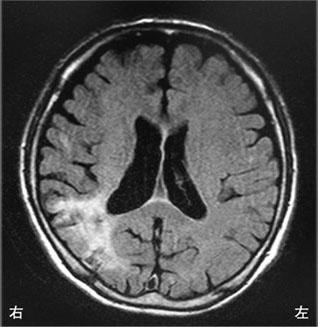

60歳の男性。7年前から歩行時にふらつきを自覚し、6年前から話し方が単調で途切れ途切れとなり膀胱直腸障害と起立性低血圧を認めた。四肢の固縮や振戦が徐々に進行し、2年前から車椅子で移動するようになった。最近、声が小さくなり呼吸困難感を訴えるようになった。頭部MRIのFLAIR画像で水平断(A)および矢状断(B)を示す。この疾患で合併する可能性が高いのはどれか。

声帯麻痺

下方注視麻痺

他人の手徴候